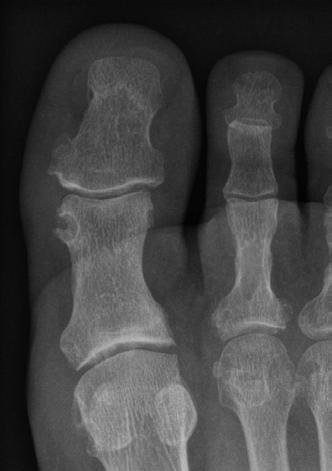

La goutte devient chronique lorsqu’au moins deux crises se produisent par année, pendant une longue période, ou lorsque des inflammations articulaires sont présentes dans l’intervalle, sans provoquer de crise de goutte. Une goutte chronique peut déformer les articulations et détruire les os et le cartilage articulaire. C’est la raison pour laquelle la goutte de l’articulation du gros orteil s’accompagne souvent d’un hallux valgus, aussi communément appelé « oignon ». L’hallux valgus limite les mouvements et est douloureux lorsque la personne bouge ou sollicite cette zone.

Alors que la goutte aiguë (à gauche) est visible à l’œil nu, il faut une radiographie pour constater les effets destructeurs de la goutte chronique.

ou les gaines tendineuses, mais aussi dans le tissu conjonctif, c’est-à-dire dans les tendons, les os et le cartilage. Des nodules goutteux à taches blanches sont bien visibles et palpables dans les oreilles, les coudes, les doigts ou les paupières. Ils sont gênants, mais provoquent rarement des symptômes.

Lorsque les résultats des analyses de laboratoire soulèvent un doute, on les complète par des clichés d’imagerie. Les radiographies montrent par exemple une dégradation de la masse osseuse ou du cartilage. Ces lésions sont généralement présentes depuis longtemps ; elles témoignent de crises de gouttes récurrentes. Les nodules goutteux (tophi) et les accumulations d’urate à la surface du cartilage s’observent facilement à l’échographie ou au scanner spectral en double énergie (DECT).